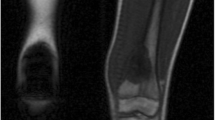

Normal age-related bone marrow conversion within the long bone. Red to yellow marrow conversion occurs in a predictable manner throughout childhood and adolescence. The adult marrow pattern is reached around 25 years of age, characterized by red marrow confined to the axial skeleton and proximal femora and humeri. During infancy there is hematopoietic marrow (red marrow) throughout the long bones. The secondary ossification centers quickly convert from red to yellow marrow. In childhood, the marrow conversion starts in the center of the long bones and progresses proximally and distally toward the metaphysis